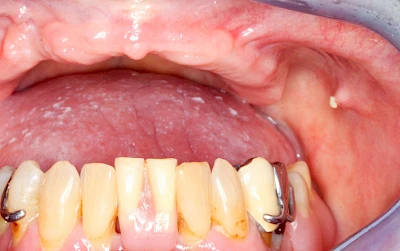

Mandelstein

Mandelsteine (Tonsillenstein oder auch Tonsillolith) sind Reste von Gewebe, Speisen, Entzündungszellen und Bakterien können vereinzelt im Bereich der Gaumenmandeln beobachtet werden. Ggf. sollten die aktuellen Mundpflegemaßnahmen überprüft und ggf. angepasst werden.